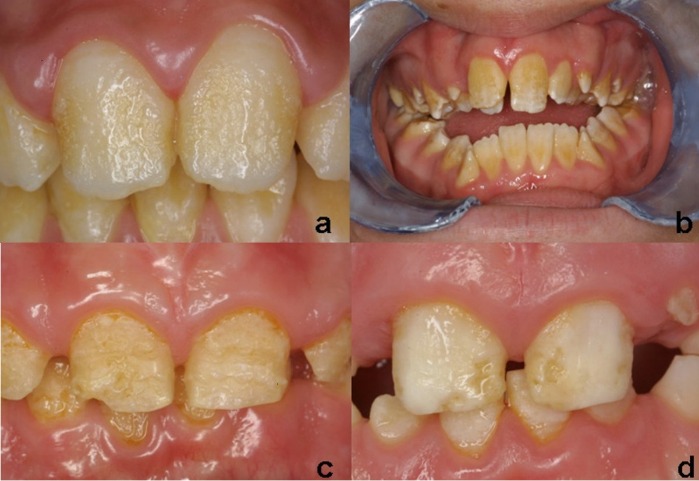

- Гипопластическая форма (рис.1)

Имеются количественные изменения в процессе формирования матрицы. То есть, эмаль правильно сформировалась, но она имеет недостаточную толщину. Эта форма наследуются аутосомно-доминантно/рецессивно и Х-сцепленно. Поражённые участки эмали чаще локализованы на вестибулярной (щёчной) поверхности зубов. Видны ямки (или овальные углубления) различных размеров и глубины, бороздки различной протяжённости, имеющие продольное направление. Эмаль достаточно твердая, и её поверхность может быть гладкой, шероховатой, гранулообразной, но непоражённые участки сохраняют свой блеск. Стоит отметить, что глубина дефекта определяет интенсивность окраски эмали (чем глубже дефект, тем интенсивнее окрашивается истонченная эмаль и обнажённый дентин). Эмаль становится светло-желтой или светло-коричневой. Наблюдается гиперестезия (на холод и горячее), скол эмали, уменьшение величины зуба, тремы между зубами (не всегда). Гипопластическая форма встречается чаще остальных форм НА (61,2 %)

Рисунок 1 | Гипопластическая форма

Рисунок 2 | Гипоматурационная форма

Рисунок 3 | Гипоминерализованная форма